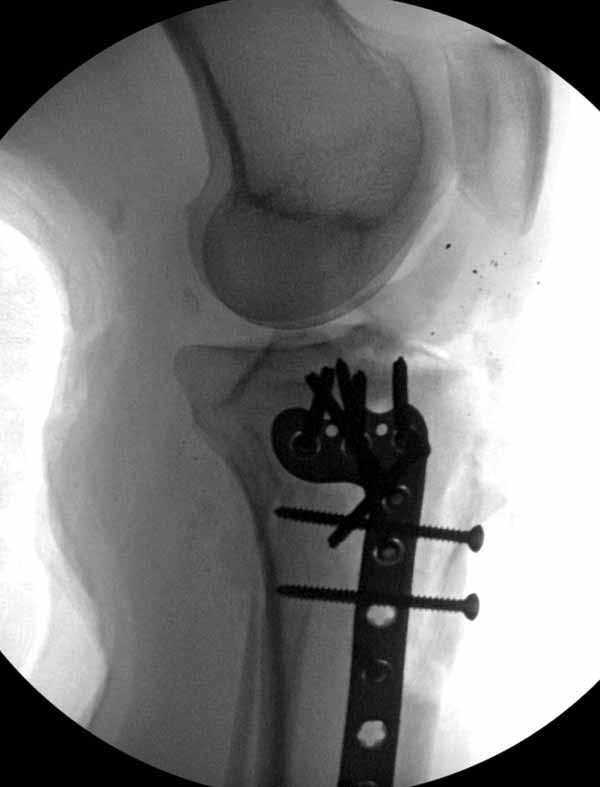

Из всех перечисленных методов подходит вариант пластики аутокостью и усиление (арматура) шурупами. Основная задача сохранить интактную медиальную стенку и латеральный кортекс. Доступ передне-латеральный, но надо работать спереди шейки через небольшое окно в 10-15 мм. Фиксацию надо проводить между медиальной тонкой стенкой головки и латеральным кортексом. Каннюлированные шурупы 6.5 мм очень грубые и могут разрушить остаток стенки. Фиксировать надо кортикальными шурупами 3.5 мм, которые создадут мостик и арматуру в шейке. Провести по периметру шейки 4, и в центре пару шурупов. Во время операции и при манипуляции соблюдать осторожность, в любой момент может наступить стресс перелом. Заранее надо заказывать длинные шурупы!